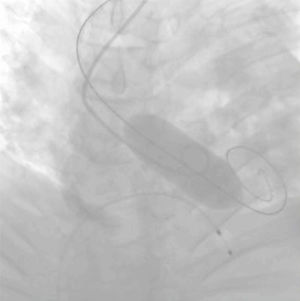

Post-dilatación (fig. 2)Cuando se trata de dirimir cuáles son los resultados clínicos de pacientes sometidos o no a post-dilatación, la evidencia de la que disponemos38-45 nace, una vez más, de estudios no aleatorizados y sesgados. Ello explica la disparidad de sus conclusiones y traduce la necesidad de interpretarlas con cautela.

Existen numerosos escenarios que motivan el planteamiento de la post-dilatación tras el implante de una TAVI. Quizá el más importante (por su elevada frecuencia y repercusión negativa) sea la reducción de la severidad de una RPV, pues el baloneo promueve una expansión óptima de la prótesis (figs. 3 y 4). Con ello, también se consiguen un aumento del área valvular efectiva, una disminución de los gradientes y, en consecuencia, una reducción del mismatch (que se ha asociado a una mayor incidencia de trombosis valvular clínica y subclínica)46.

Regurgitación perivalvularLa RPV es consecuencia de una aposición incompleta de la prótesis al anillo nativo por intensa calcificación y excentricidad anular, infra, sobredimensión o posicionamiento inadecuado de la TAVI.

Li et al.49 realizaron un estudio computacional in vitro que simulaba el implante de una TAVI autoexpandible mediante dos modelos diferentes de dilatación (pre y post) con objeto de analizar su impacto en los resultados (estrés vascular, morfología del stent y RPV). Sus conclusiones argumentan que la pre-dilatación genera menor impacto que la post-dilatación, que puede mejorar la morfología protésica y, con ello, el funcionamiento y la durabilidad valvular. También optimizaría la adhesión al stent, con la subsiguiente reducción de la RPV en más del 30%.